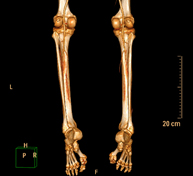

- Lower leg rotational study using CT [patella, tibial tuberosity to trochlear groove (TT-TG) distance]

Radiological examination based on an X-ray system and detectors that rotate around the patient, reconstructing the images by computer (multidetector computed tomography - MDCT) to calculate a series of measurements at the hips, knees and ankles with a view to solving problems affecting the rotation and angulation of the lower limbs.